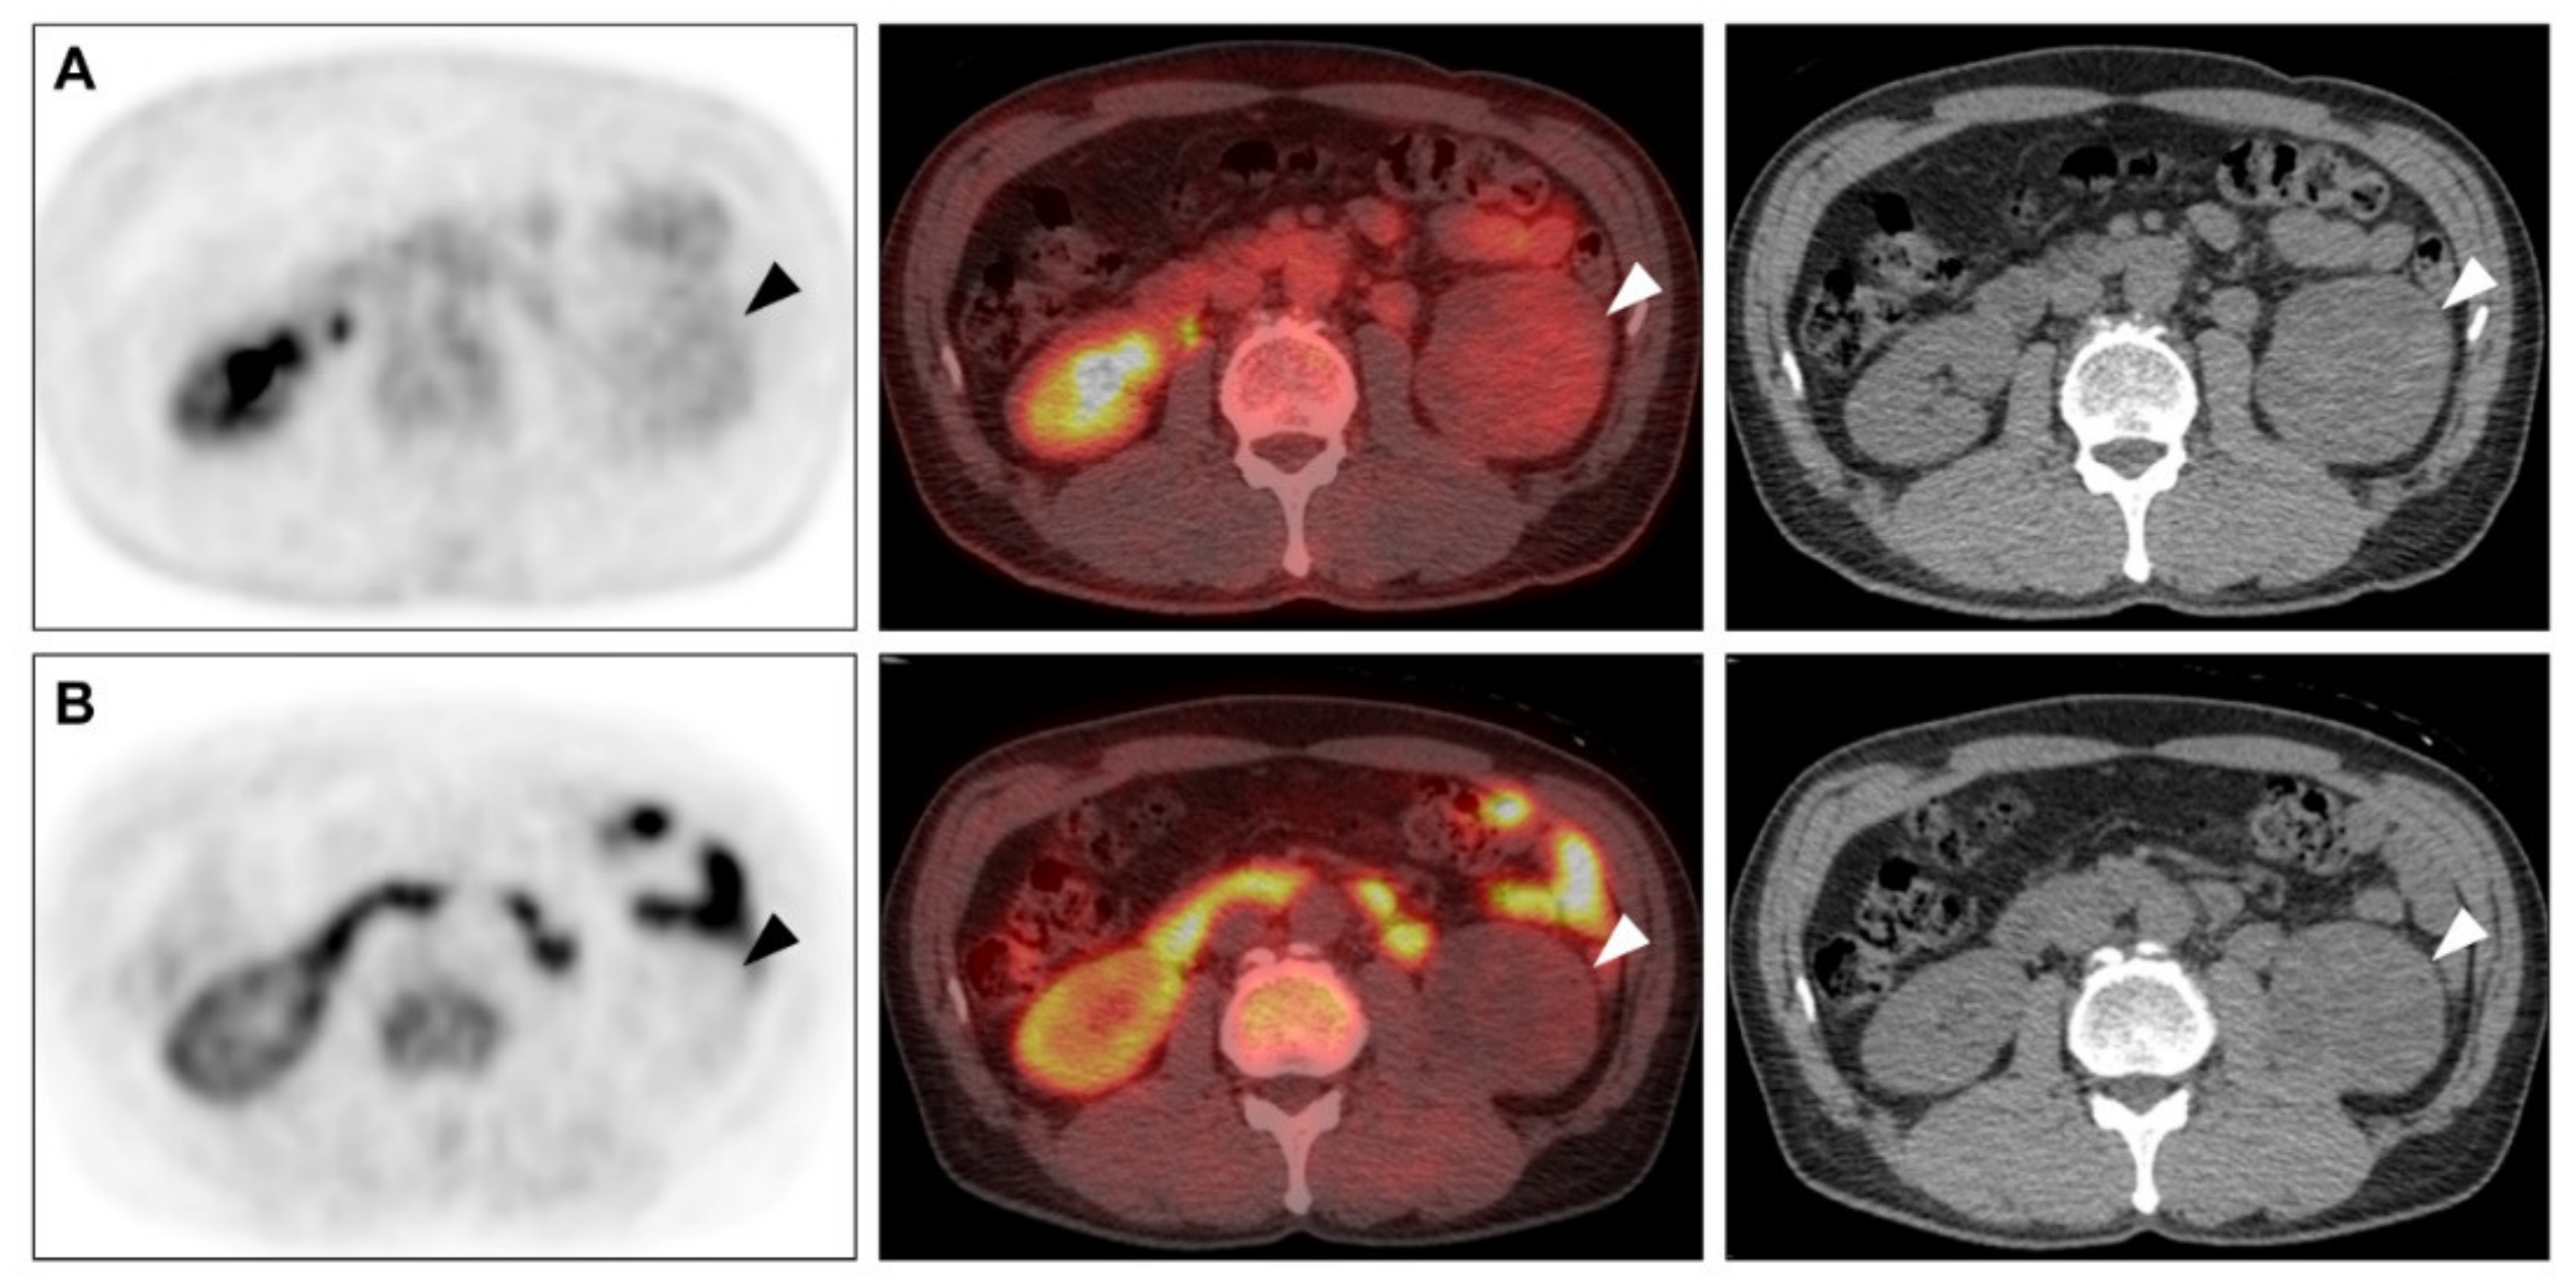

2.3. Comparison of F-18 FDG and C-11 MET Uptake in the Primary Tumour and Histopathological Findings

2.4. Comparison of Detection of Extra-Renal Metastases between Conventional Imaging and PET/CT